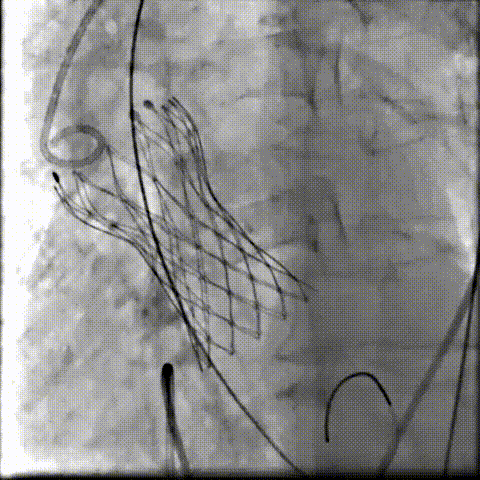

术中影像

根部造影可见返流,23mm球囊预扩张

无窦侧严重钙化及融合影响,

瓣膜(AV29)释放不稳出现反复上跳,2次回收尝试

重新定位释放,

钙化及融合挤压导致瓣膜(AV29)下滑位置偏深

第三次回收重新定位

工作位造影位置良好,完全脱钩释放瓣膜(AV29)

考虑支架腰部挤压,23mm球囊充分后扩后形态良好,

极微量瓣周漏